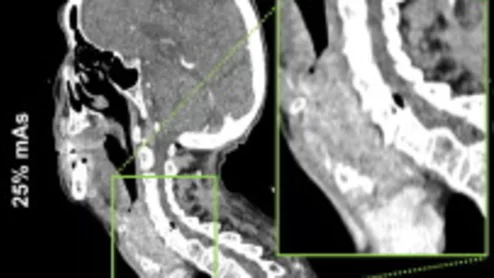

deep learning algorithm slashes radiation dose during neck CT scans

And the dose reduction can be achieved without sacrificing image quality, a new analysis shows.